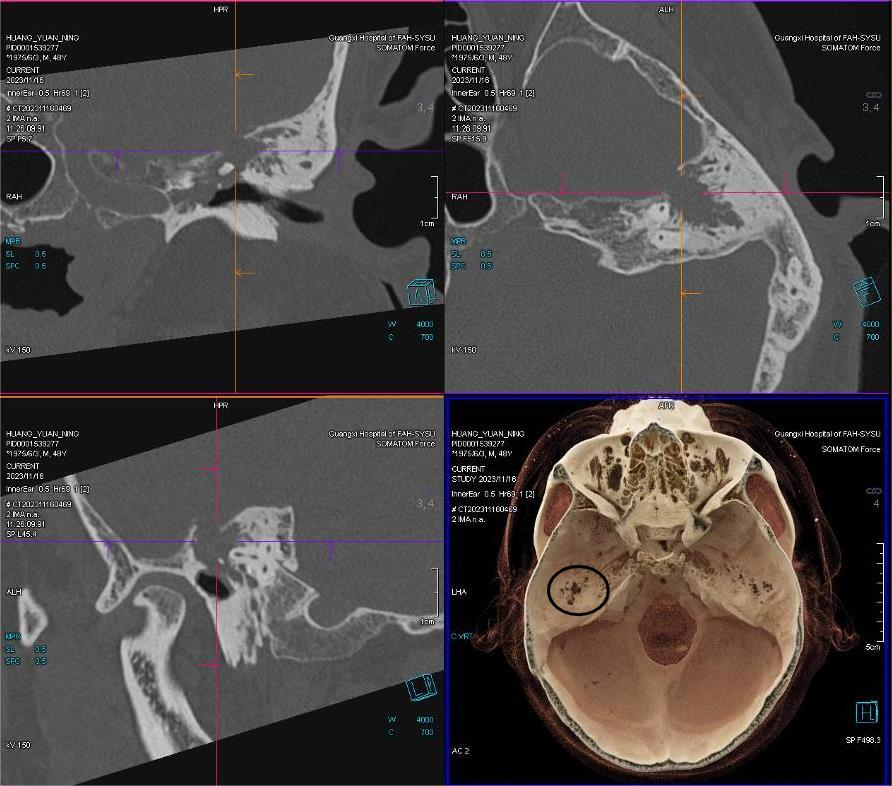

▲CT三维重建显示脑脊液耳漏缺损部位及大小(黑色圆圈示左侧中颅底缺损)。

入院后,李健教授带领团队为黄先生做了全面检查,诊断为脑脊液耳漏(左)、传导性耳聋(左),需手术治疗封堵颅底缺损修补硬脑膜裂口,防止颅内感染。耳鼻咽喉头颈外科王涛主任医师针对患者情况,联系了神经外科、呼吸与危重症医学科、重症监护病房、影像学多学科进行多学科会诊,并为患者制定周全治疗方案。